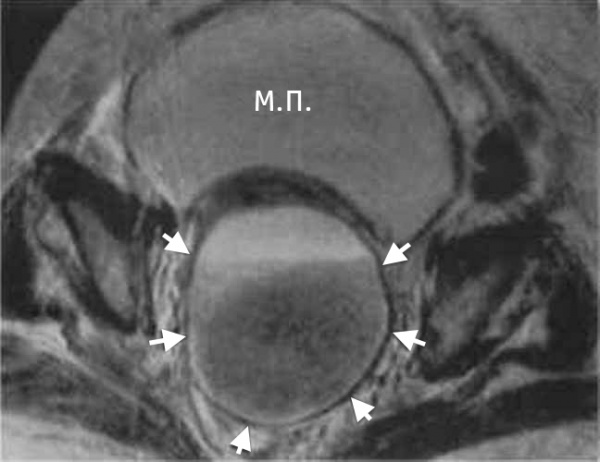

16 Диагностика Рентгенологическая картина мало информативна. Большую роль в диагностике играют ультразвуковое исследование, магнито резонансная томография. При ректальном исследовании выявляют зияние сфинктера прямой кишки, дряблость стенок ампулы, нависание передней стенки ампулы.

Абсцесс дугласова пространства – инкапсулированный гнойный очаг, расположенный в маточно-прямокишечном (прямокишечно-пузырном) углублении малого таза. Клиника характеризуется неспецифическими проявлениями (интоксикацией, фебрильной температурой, ознобами) и местной симптоматикой (болью в нижних отделах живота, дизурическими явлениями, частыми позывами на дефекацию). Диагностика включает ректальное и вагинальное (у женщин) исследование, УЗИ малого таза, КТ, пункцию гнойника через прямую кишку или задний свод влагалища. Лечение абсцесса дугласова пространства заключается в его вскрытии через прямую кишку или влагалище, дренировании и санации, проведении антибиотикотерапии.

Пальпаторно определяется болезненность в области малого таза, локальное напряжение мышц, положительный симптом Щёткина — Блюмберга. При ректальном или влагалищном исследовании выявляется болезненный тугоэластический инфильтрат с размягчением и флюктуацией в центре. У женщин абсцесс дугласова пространства пальпируется выше шейки матки, определяется нависание заднего свода влагалища.

КТ органов малого таза. На снимке: абсцесс, отграниченный стенкой (А), прямая кишка (R), матка (U), мочевой пузырь (B)

В сложно дифференцируемых случаях может потребоваться выполнение компьютерной томографии, МРТ. Для окончательного распознавания абсцесса дугласова пространства прибегают к диагностической пункции гнойника под ультразвуковым наведением через прямую кишку либо задний свод влагалища. Полученное гнойное содержимое подвергается бактериологическому исследованию.